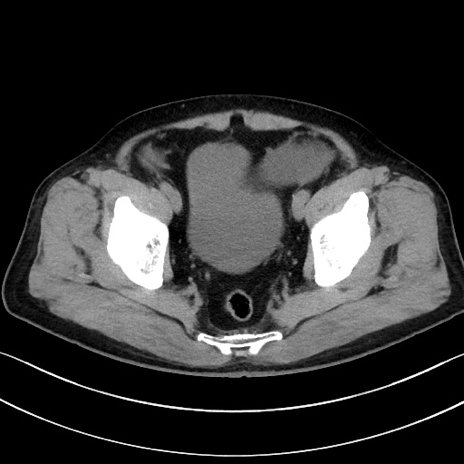

症例15(横断像)

【症例】70歳代男性

【主訴】腹痛

【現病歴】今朝から腹痛あり。全体的に痛い。特に左上の方。排ガスが今日はない。冷や汗が出る。

【既往歴】直腸癌術後

【身体所見】左側腹部〜上腹部に圧痛あり。腹膜刺激症状明らかなではない。軽度反跳痛。左下腹部に術後瘢痕あり。

【データ】WBC 7700、CRP 0.02